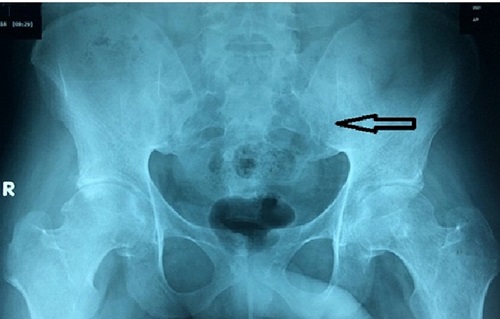

Hình ảnh tổn thương của bệnh nhân khi chụp X-quang - Ảnh: Công lý |

Ngày 18/8, thông tin từ Bệnh viện Nhân Dân 115 (TP.HCM) cho biết, vừa điều trị thành công cho nam thanh niên suýt tàn phế do bị viêm cột sống dính khớp nhưng điều trị không đúng cách.

Trước đó, bệnh nhân nhập viện trong tình trạng bất động ở tư thế nằm sấp, ăn uống và vệ sinh tại chỗ kèm đau lưng, đau khớp háng hai bên.

Bệnh nhân cho biết, rơi vào tình trạng đau lưng, đau lan xuống hai mông, đi lại hạn chế cách đây 5 năm. Bệnh nhân đã điều trị tại một bệnh viện địa phương với chẩn đoán đau thần kinh tọa/thoát vị đĩa đệm cột sống thắt lưng.

Do điều trị không liên tục, tình trạng bệnh không cải thiện. Sau đó, bệnh nhân chuyển sang điều trị bằng thuốc nam nhưng cũng không khá hơn. 2 năm sau, người này khám tại một bệnh viện khác với chẩn đoán viêm cột sống dính khớp nhưng không cải thiện nhiều sau điều trị nên ngưng.

Bệnh nhân tiếp tục tìm đến thầy lang địa phương và được điều trị bằng phương pháp kéo giãn tứ chi và nằm bất động suốt 6 tháng. Tuy nhiên, do tình hình không cải thiện, bệnh nhân tìm đến Bệnh viện Nhân dân 115.

Tại bệnh viện, các bác sĩ chẩn đoán đây là trường hợp viêm cột sống dính khớp và quyết định điều trị bằng thuốc đặc hiệu cho bệnh nhân. Sau 3 tuần điều trị bằng thuốc đặc hiệu, bệnh nhân có thể đi lại bằng nạng. Sau 6 tuần điều trị, bệnh nhân có thể tự đi lại dễ dàng.

Theo BSCKI Huỳnh Thị Tố Khanh - Khoa Cơ Xương Khớp, Bệnh viện Nhân Dân 115, bệnh viêm cột sống dính khớp là bệnh tự miễn, có các biểu hiện như đau lưng kiểu viêm, mệt mỏi, sưng nóng đỏ đau các khớp ngoại biên, có thể kèm rối loạn tiêu hóa. Bệnh thường bị nhầm lẫn với đau lưng do vận động nặng, do sai tư thế hay đau thần kinh tọa do đặc điểm đau lưng lan xuống mông.

Nếu không phát hiện và điều trị sớm, viêm cột sống dính khớp sẽ gây nhiều biến chứng nặng nề. Bệnh có thể gây tàn phế, mất khả năng lao động khi bệnh nhân đang ở độ tuổi trẻ, tạo gánh nặng cho gia đình và xã hội.

“Riêng trường hợp nói trên, nếu bệnh nhân tiếp tục điều trị bằng cách kéo giãn tứ chi theo phương pháp của thầy lang sẽ dẫn đến tình trạng cứng khớp tay chân, không thể đi lại”, BS Tố Khanh cho hay.